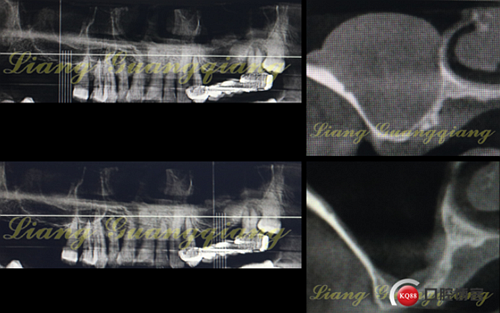

這是一周前拔牙前X光片,上頜竇內(nèi)大囊腫直徑遠遠>10mm。如何處理?送耳鼻喉?接下來就是預約住院,上頜竇內(nèi)手術清掃?;謴投嗑貌恢笃谑欠窨梢岳^續(xù)提升?真不好說。

神奇了吧,右側(cè)那么大的囊腫竟然消失的無影無蹤了.

有很多老師擔心,后期囊腫是不是還會復發(fā)?大量臨床病例術后長時間跟蹤X光復查,未見復發(fā)。但有少量病例出現(xiàn)術后上頜竇感染癥狀,可能是植入的骨粉污染造成的,當然在沒有囊腫的病例中、在沒有出現(xiàn)上頜竇膜穿孔的情況下同樣會發(fā)生上頜竇感染,具體問題具體分析。